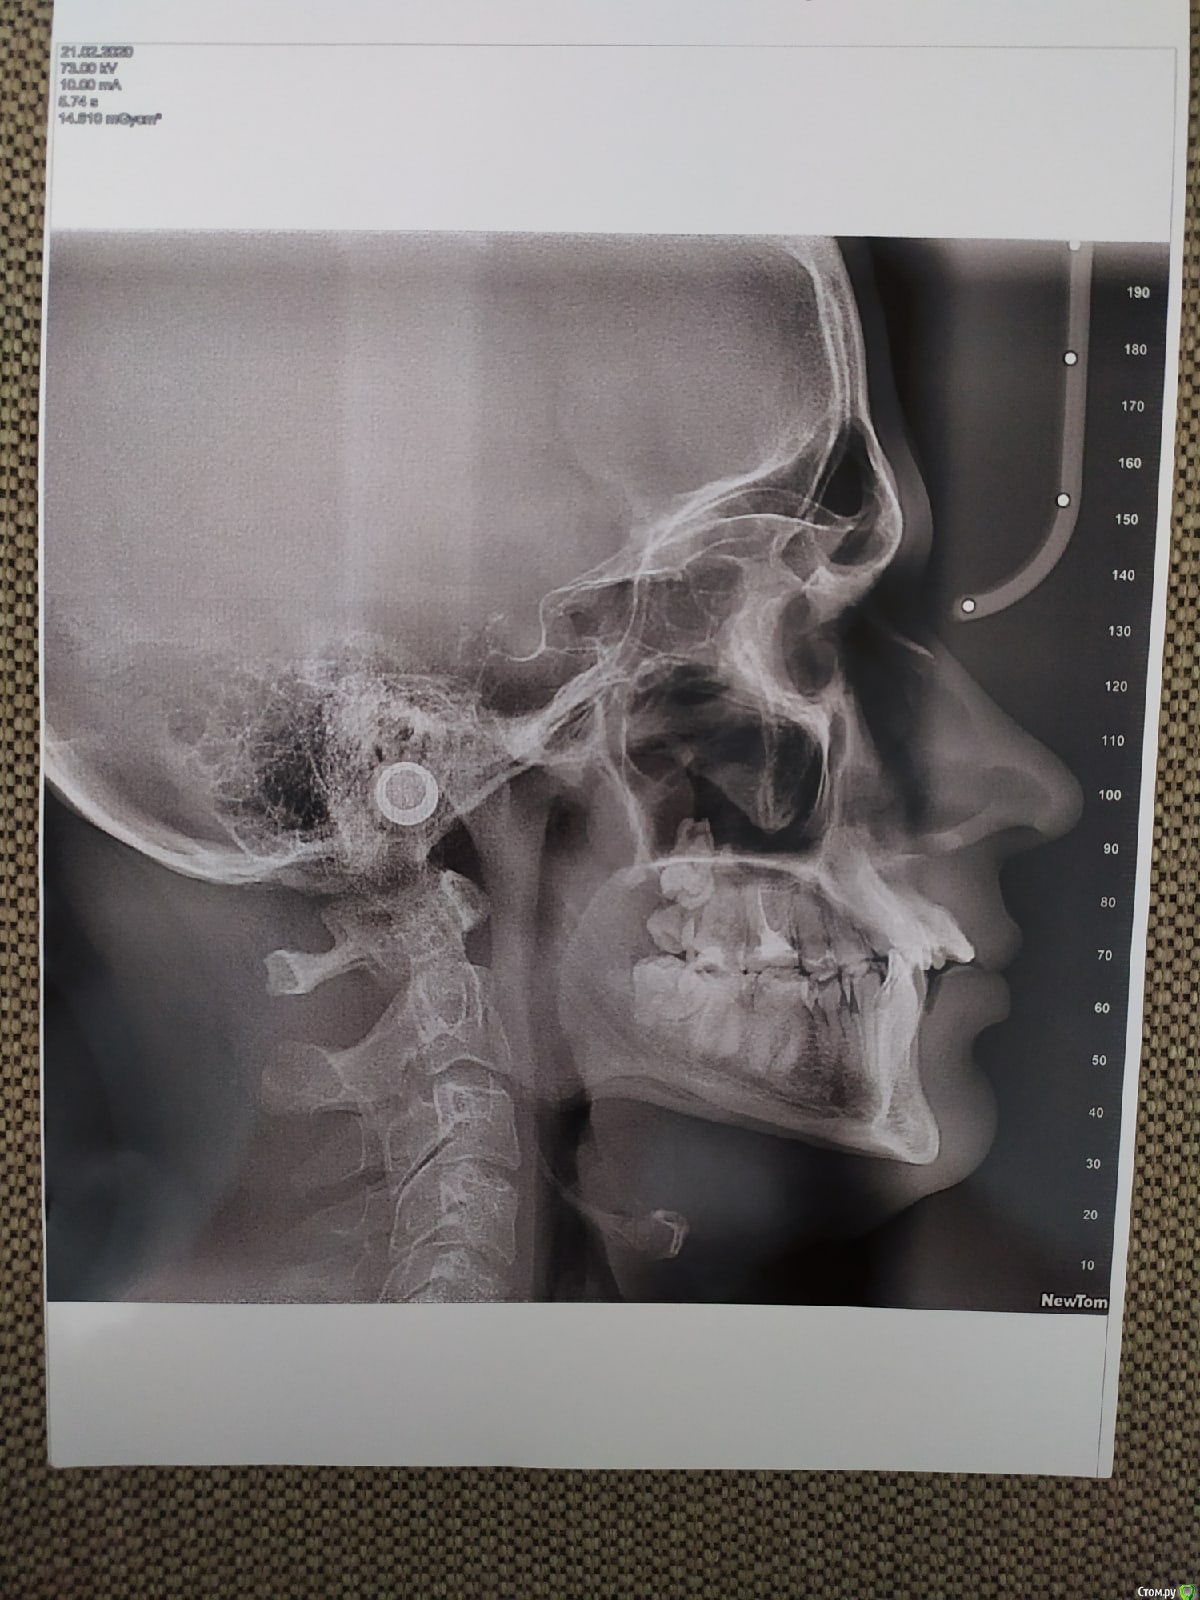

myshape Опубликовано 1 мая, 2020 Поделиться Опубликовано 1 мая, 2020 Здравствуйте! Историю моих зубов раскрывать не буду. Скажу только, что 2 месяца назад решился ставить брекет систему. После посещения рекомендованного мне ортодонта, направили на трг с диагностикой. Снимок прикрепляю.В итоге успел удалить 4 восьмерки и поставил сегодня БС Дэймон QИ тут меня накрыли сомнения и тревожные мысли после того как начитался про мой дистальный прикус. Вычитал, что это может быть скелетная проблема, а не только зубная. И надо применять хирургическое вмешательство. Теперь думаю, что удаление восьмерок было недостаточно и начал сомневаться в компетентности врача.Конкретно смущает то, что передние верхние резцы так сильно поданы вперед примерно на 45 градусов . И БС может усилить этот наклон.Очень хочется верить, что это мои домыслы и я стал себя накручивать. И врач знает, что делает. Но хотелось бы услышать мнение со стороны. Ссылка на комментарий